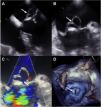

This is the case of a 67-year-old male with constitutional syndrome, fever, dyspnea, and a systolic-diastolic aortic murmur. The echocardiogram revealed the presence of aortic vegetation and a large pseudoaneurysm of anterior mitral valve location (Fig. 1-arrows) without valvular or peri-annular involvement, and positive blood cultures for Streptococcus salivaris. With a diagnosis of acute endocarditis, mitral-aortic replacement was performed under extracorporeal circulation. The left atriotomy revealed the presence of a violet giant pseudoaneurysm (Fig. 2A and B) of the entire serosanguineous anterior mitral valve (Fig. 2C and D). The postoperative period was uneventful with negative valve cultures. The association between a pseudoaneurysm post-endocarditis isolated from the anterior mitral valve leaflet without damage to the valve or mitral-aortic continuity is a rare finding. The echocardiogram is key here to select treatment and the optimal surgical time.